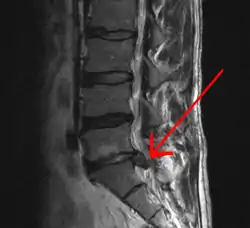

A herniated disc as seen on MRI, one possible cause of low back pain

The straight leg raise test can detect pain originating from a herniated disc. When warranted, imaging such as MRI can provide clear detail about disc related causes of back pain (L4–L5 disc herniation shown)

Imaging is indicated when there are red flags, ongoing neurological symptoms that do not resolve, or ongoing or worsening pain.[5] In particular, early use of imaging (either MRI or CT) is recommended for suspected cancer, infection, or cauda equina syndrome.[5] MRI is slightly better than CT for identifying disc disease; the two technologies are equally useful for diagnosing spinal stenosis.[5] Only a few physical diagnostic tests are helpful.[5] The straight leg raise test is almost always positive in those with disc herniation,[5] and lumbar provocative discography may be useful to identify a specific disc causing pain in those with chronic high levels of low back pain.[44] Therapeutic procedures such as nerve blocks can also be used to determine a specific source of pain.[5] Some evidence supports the use of facet joint injections, transforminal epidural injections and sacroiliac injections as diagnostic tests.[5] Most other physical tests, such as evaluating for scoliosis, muscle weakness or wasting, and impaired reflexes, are of little use.[5]